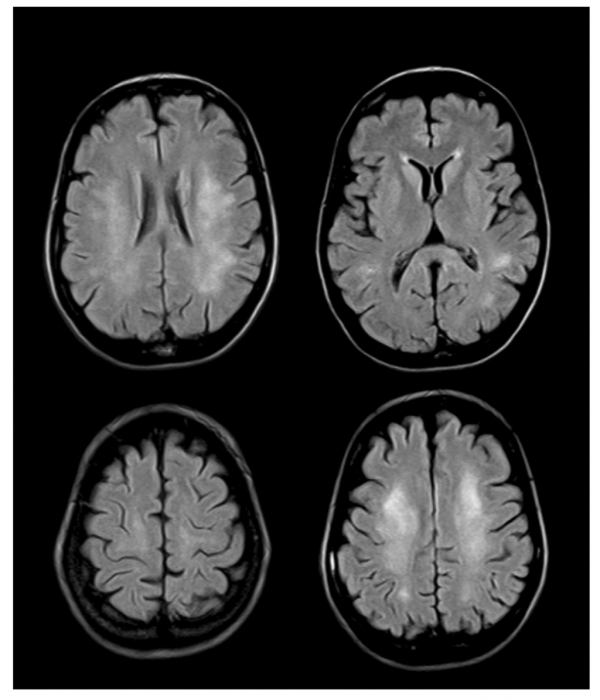

image